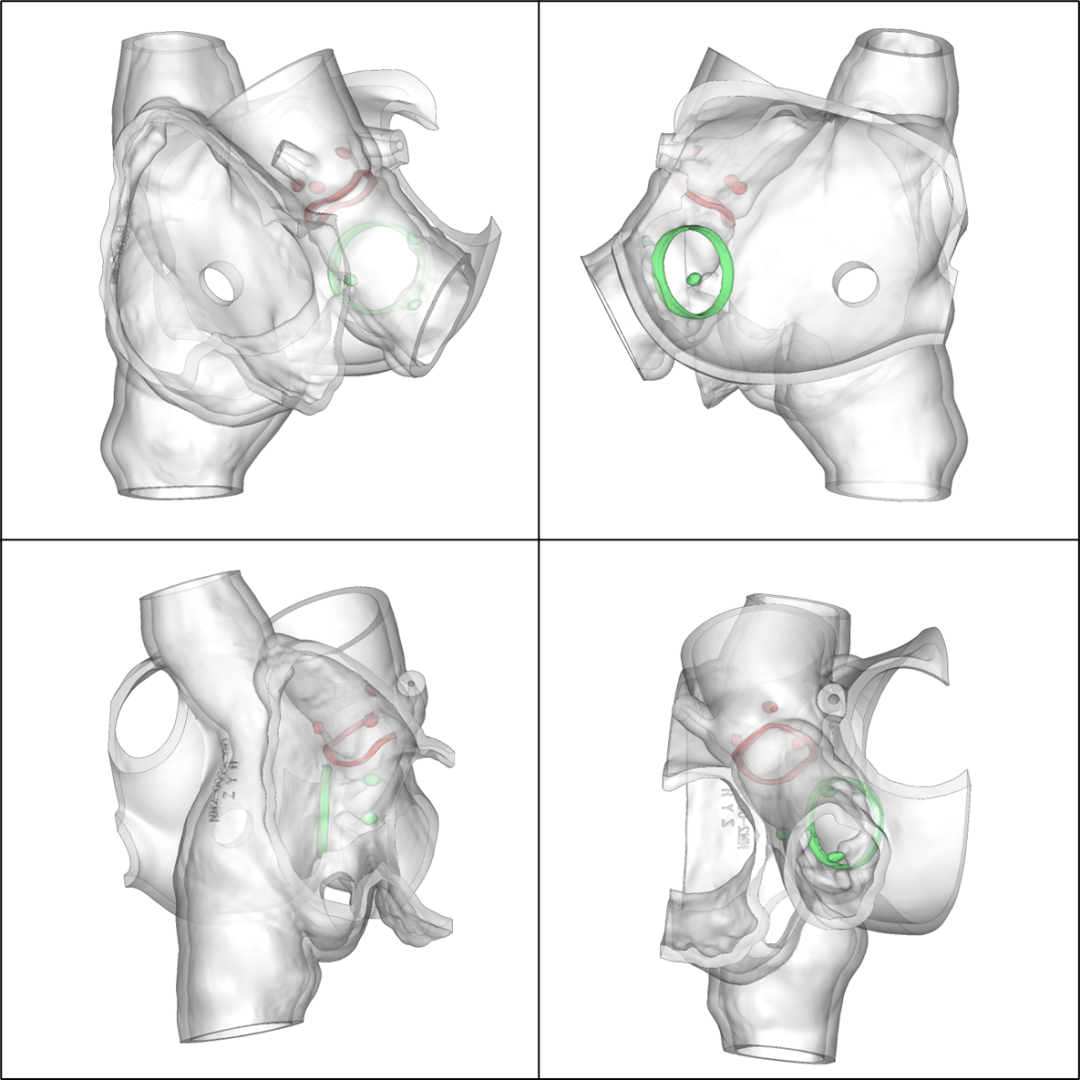

术前3D数字模型

术后3D数字模型

1.术前患者CTA影像对解剖结构的测量、3D数字模型观察以及3D打印体外模拟多模态评估技术,有助于TMVinV手术策略制定,降低手术风险;